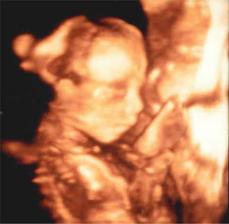

Čekáme na kuřátko březňátko